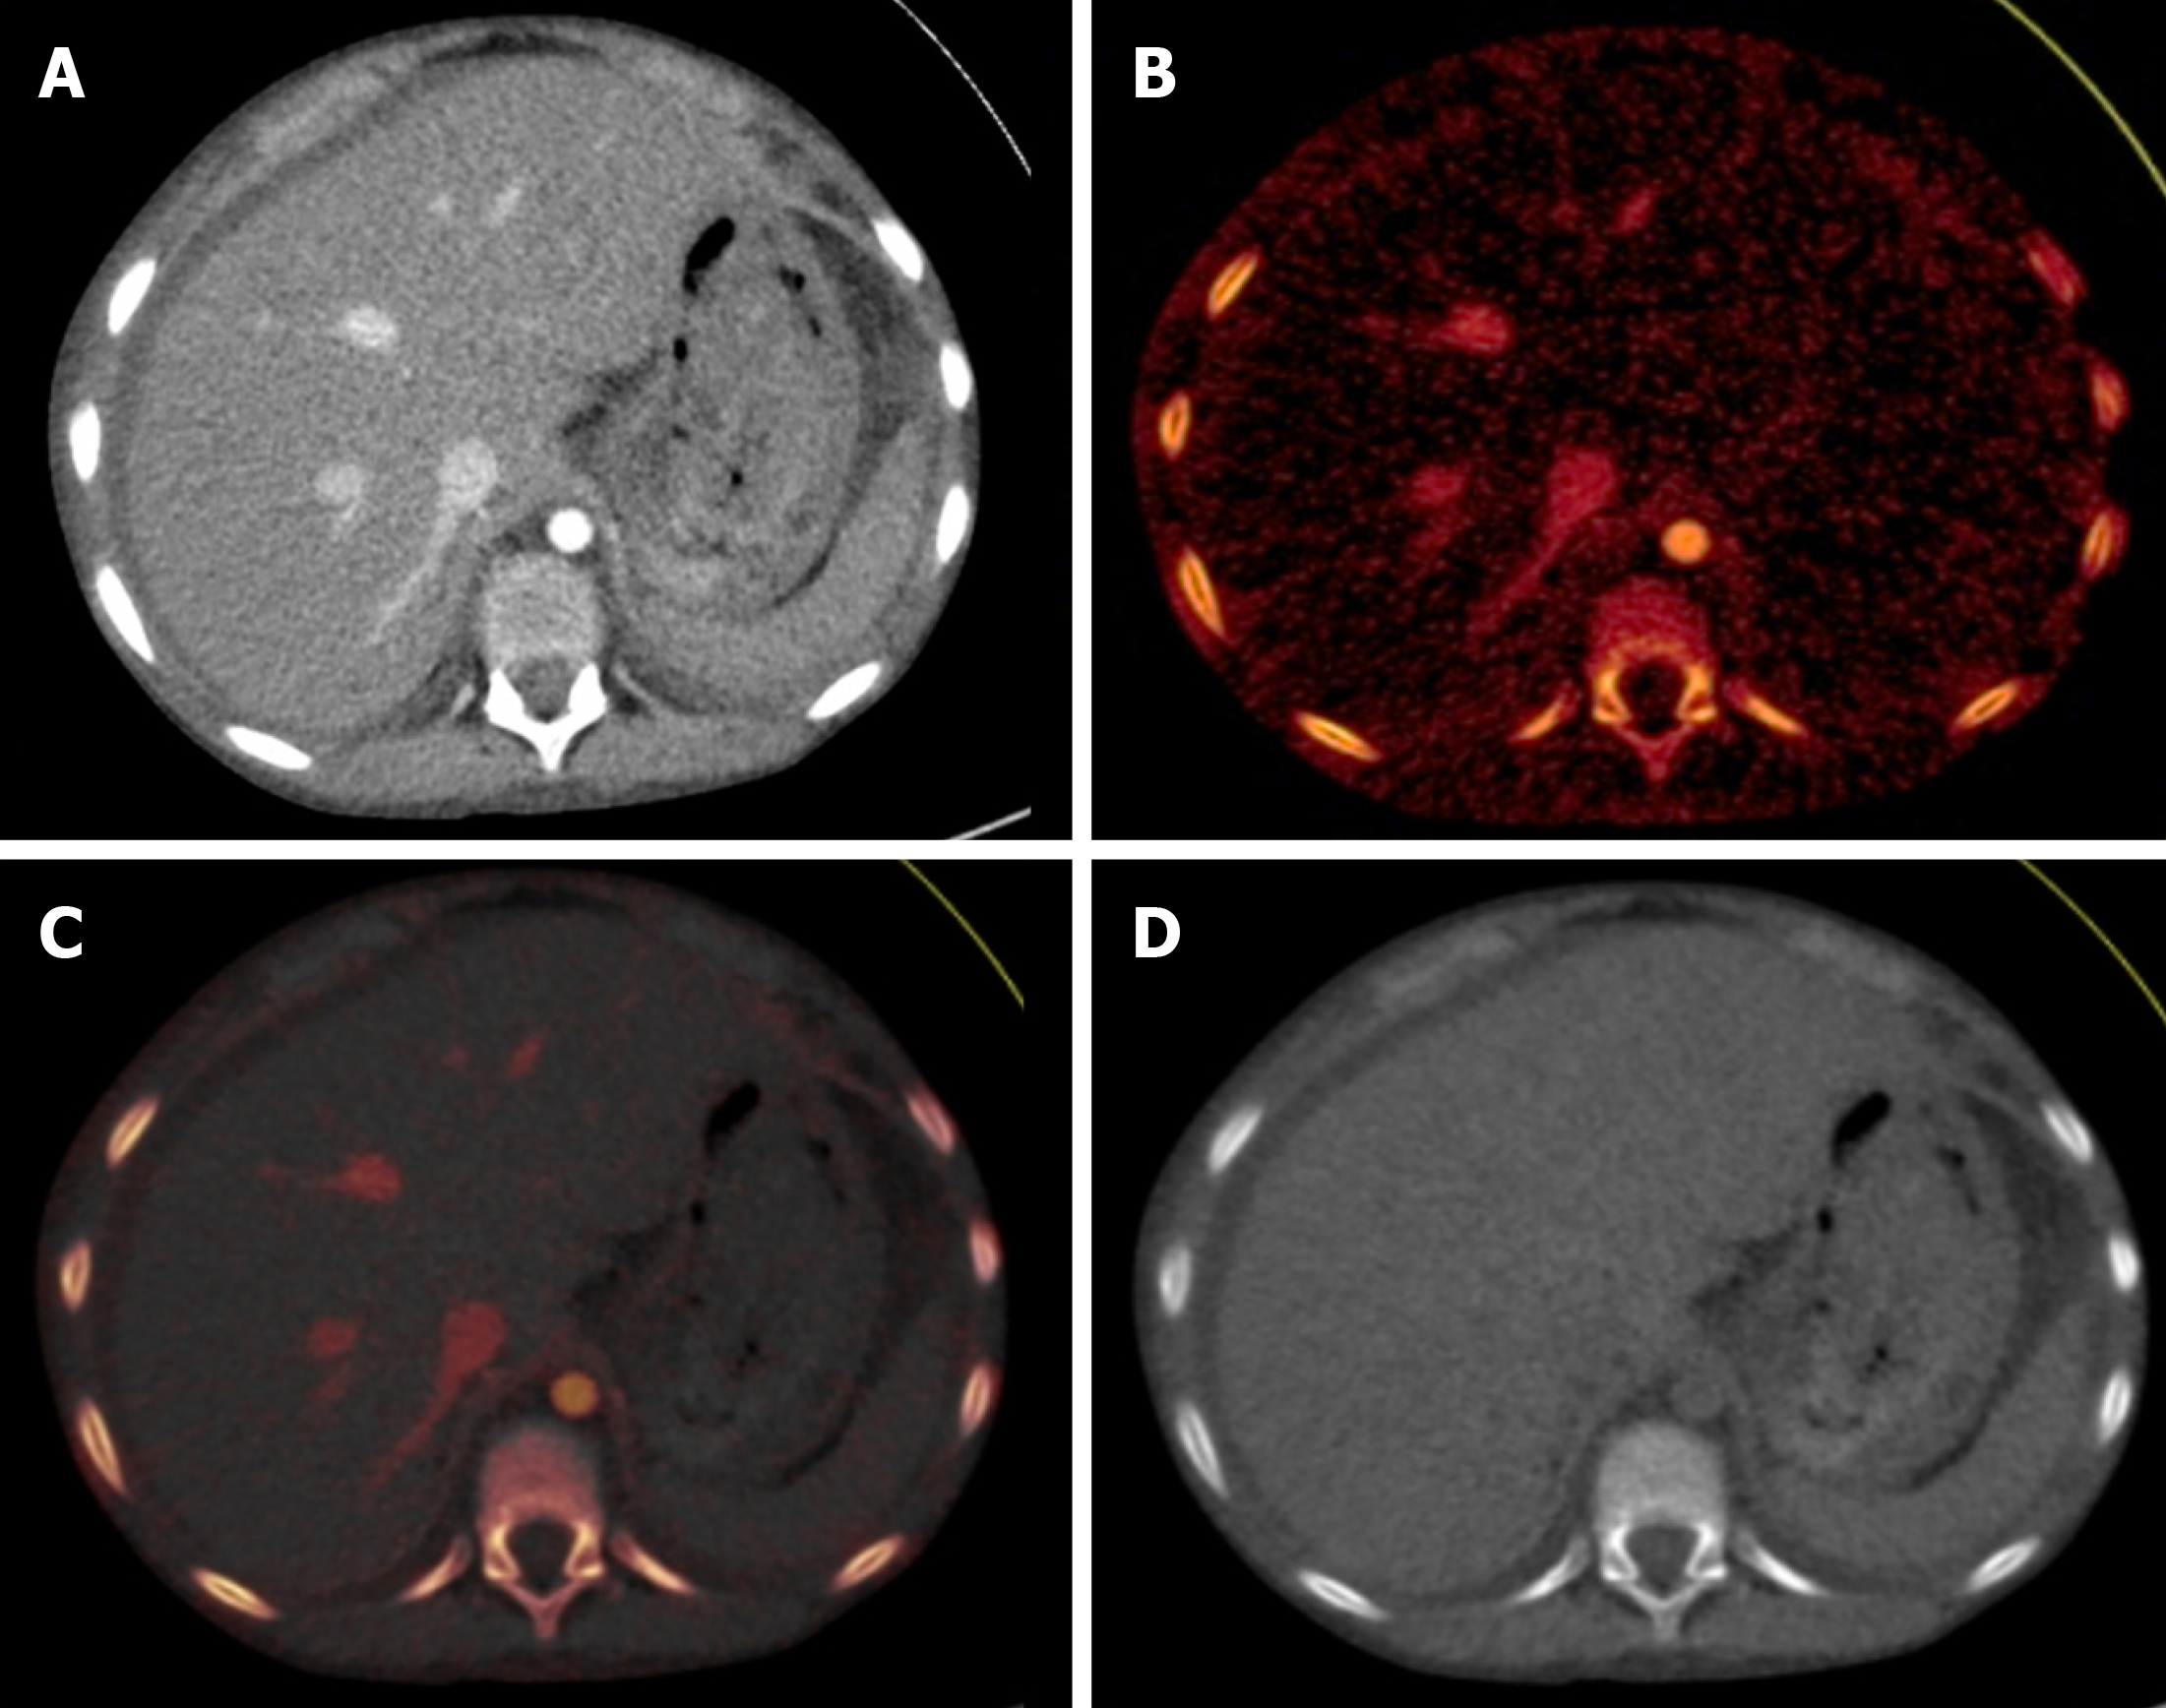

Figure 2 Different reconstructions in a dual-energy CT study.

Axial sections of the upper abdomen at the level of the liver showed normal liver. A: Blended contrast-enhanced image; B: Iodine-specific image; C: Iodine overlay image with superimposed iodine map on gray–scale virtual non-contrast image; D: Virtual non-contrast image.